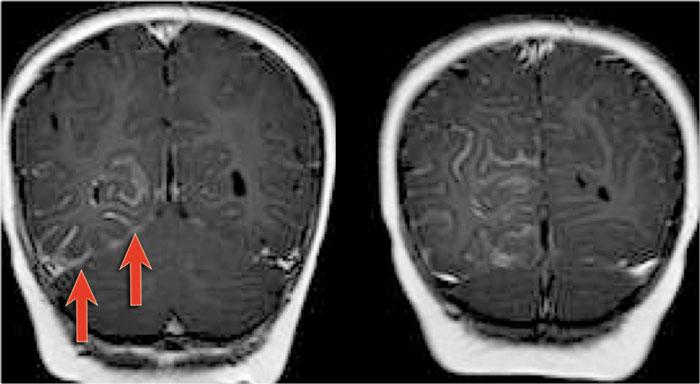

Hình ảnh T2W và FLAIR mặt phẳng coronal cho thấy xơ cứng thùy thái dương trong bên phải.

Lưu ý tình trạng mất thể tích, biểu hiện của teo não, gây giãn thứ phát sừng thái dương của não thất bên.

Tín hiệu cao trong hải mã phản ánh tình trạng gliosis.

Hình ảnh cho thấy xơ cứng thùy thái dương trong với hải mã tăng tín hiệu và teo nhỏ (mũi tên đỏ), kèm theo giãn thứ phát sừng thái dương trái của não thất bên trái.

Cũng cần lưu ý tình trạng tăng tín hiệu dưới vỏ não kết hợp ở thùy thái dương trái, gợi ý loạn sản vỏ não khu trú.